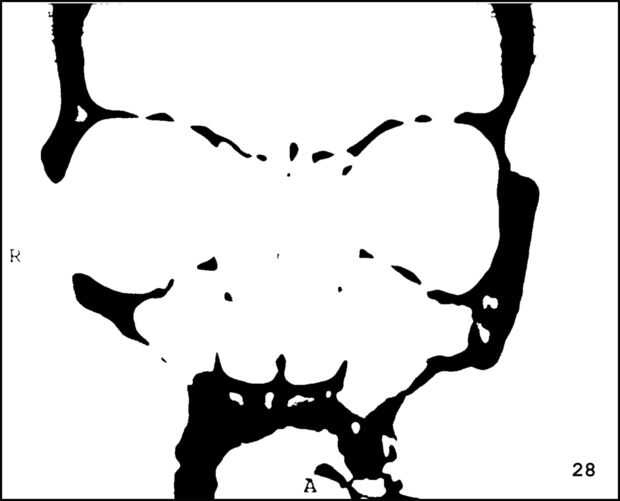

¡ Wow! Este fue por menos de 12 horas y tengo 1.000 visitas! Esto es sólo mi segundo instructable, así que estoy encantada. Decidí seguir adelante y publicar las imágenes que utiliza. Se trata de MRI de mi esposa, así que ella sólo puede tener lo mundos primer código abierto jefe. Mi lámpara utiliza solamente las primeras 16 capas, pero te di todos 34 que representa. Seguir adelante y usar estas imágenes, pero si lo haces, por favor me manden una imagen de lo que te ocurrió así que puedo hacerla sentir un poco famoso. ¡Que te diviertas!